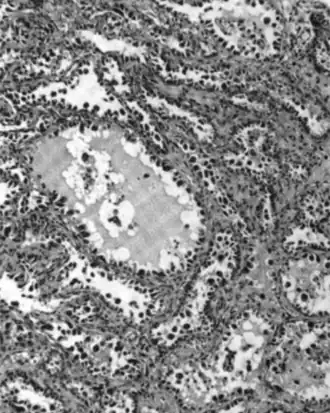

| Micrograph of a mucinous ovarian carcinoma stained by H&E | |

Mucinous adenocarcinoma

Mucinous adenocarcinomas make up 5–10% of epithelial ovarian cancers. Histologically, they are similar to intestinal or cervical adenocarcinomas and are often actually metastases of appendiceal or colon cancers. Advanced mucinous adenocarcinomas have a poor prognosis, generally worse than serous tumors, and are often resistant to platinum chemotherapy, though they are rare.[29]